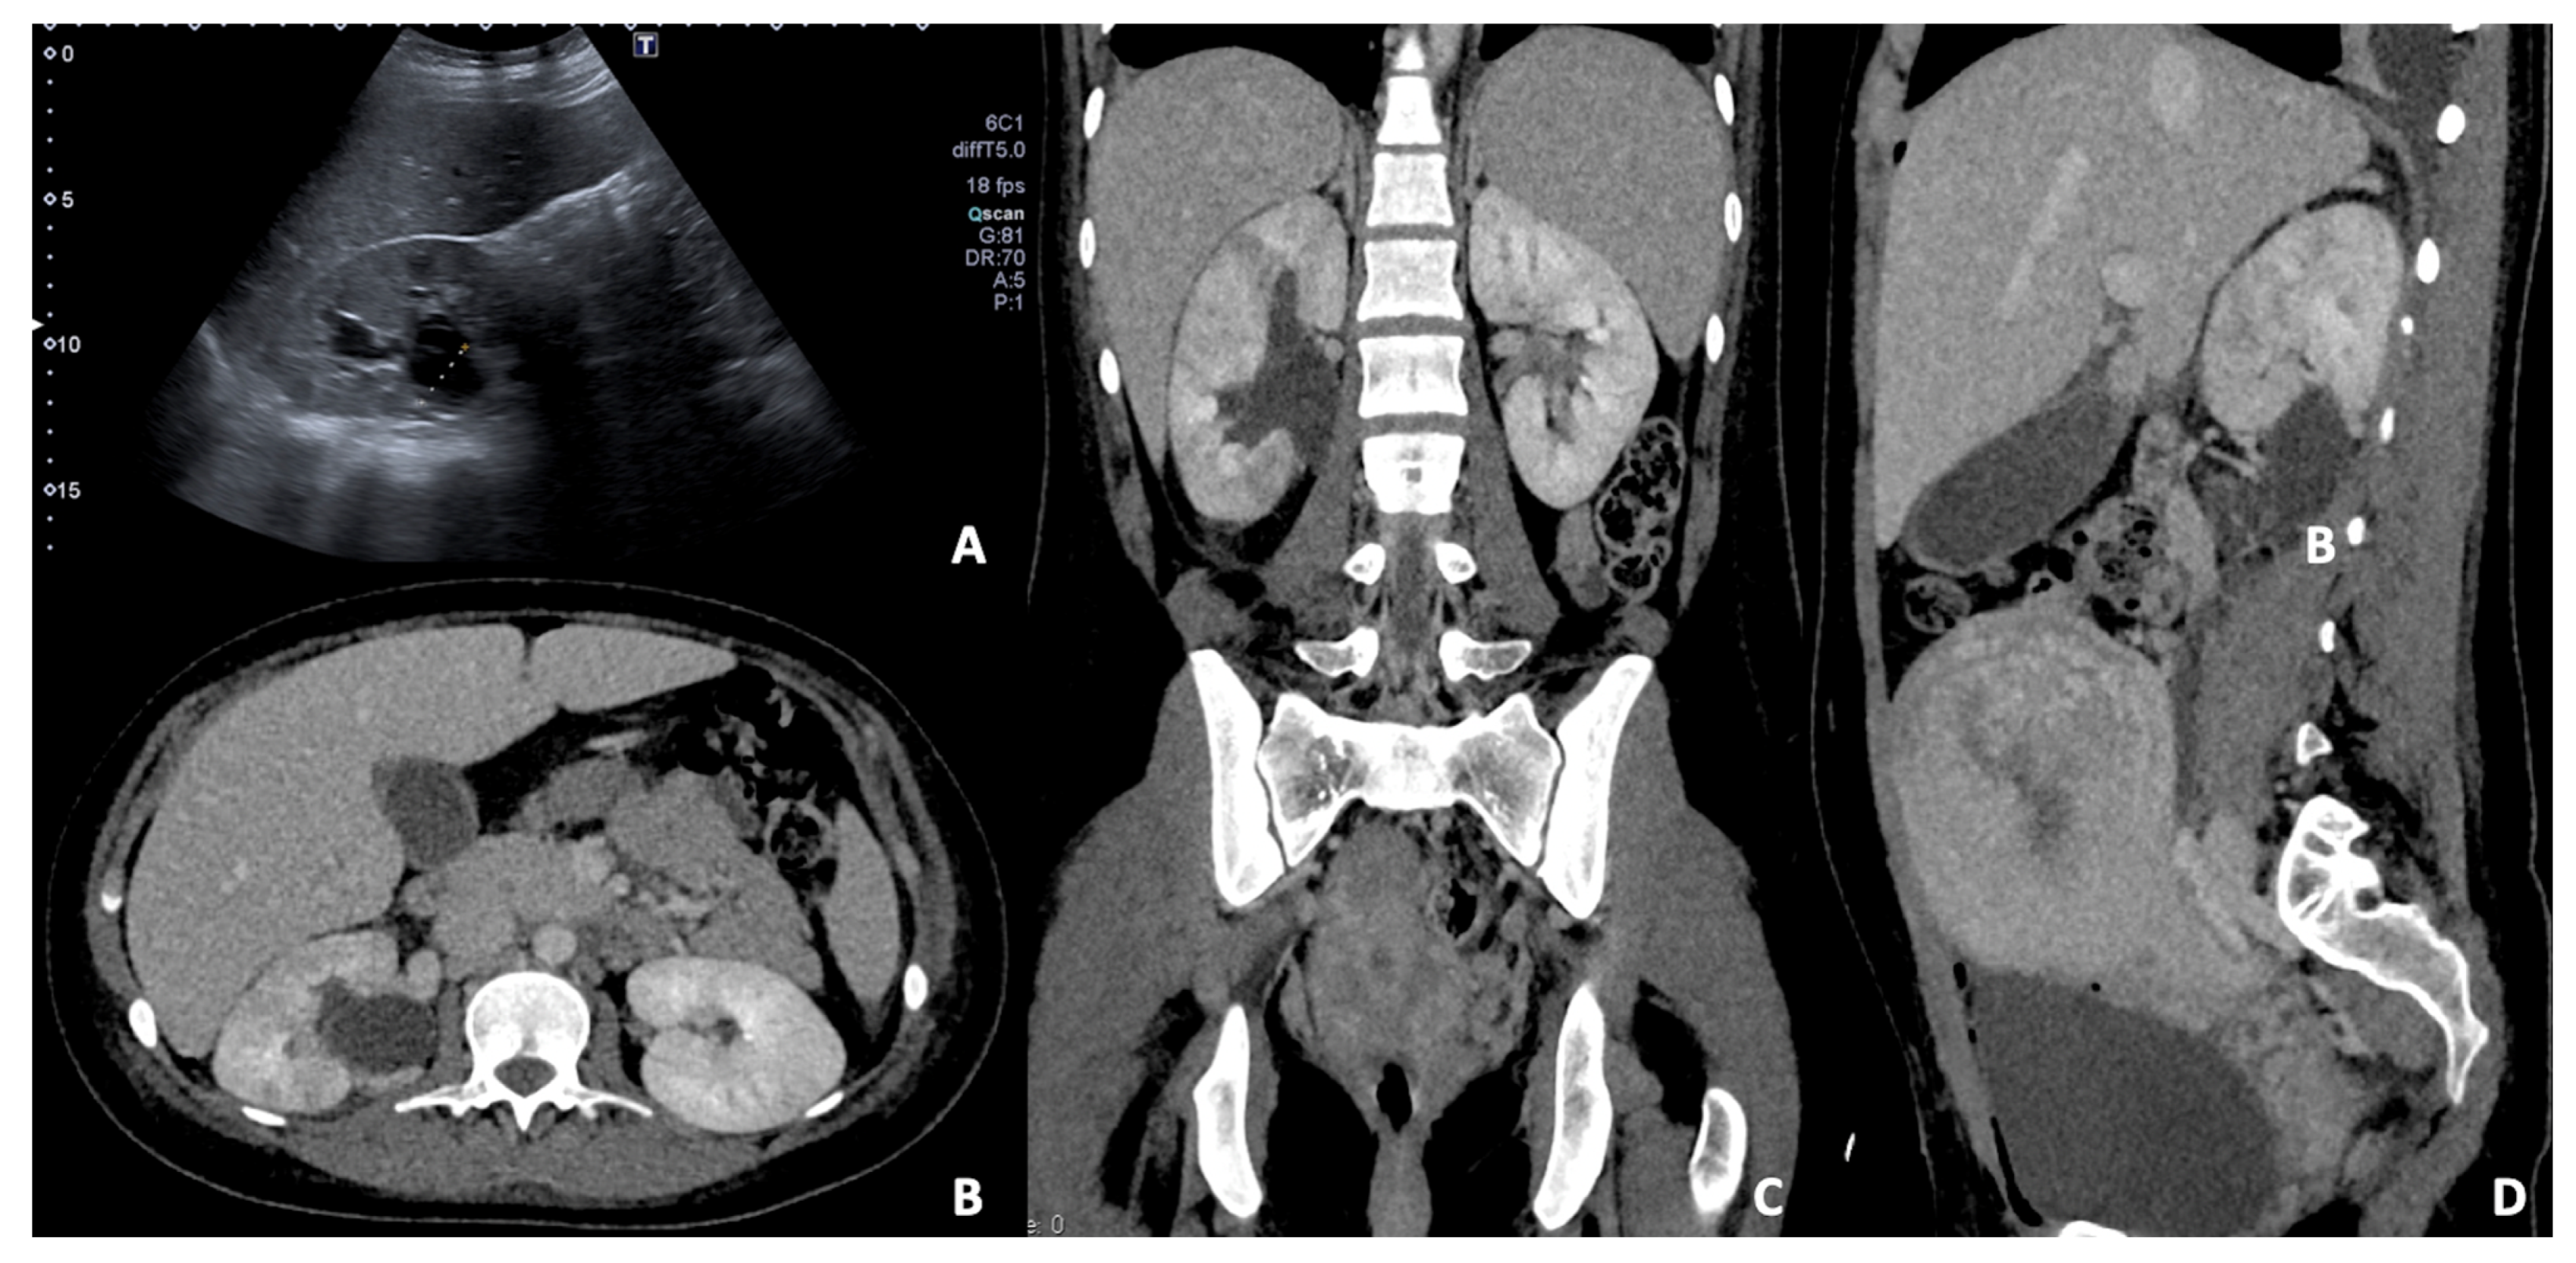

3.1. Adnexal Masses or Ovarian Cyst

3.2. Adnexal Torsion